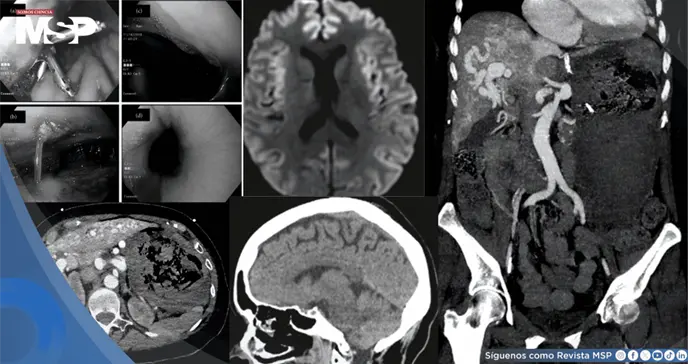

Una endoscopia urgente mostró un estómago lleno de sangre y úlceras, aunque sin un punto de sangrado activo identificable. Una angiografía por tomografía computarizada reveló las extensas malformaciones arteriovenosas en su hígado, que creaban una derivación o "shunt" anormal de la sangre, pero tampoco localizó la fuente exacta del sangrado agudo.

Aunque una tomografía computarizada inicial del cerebro fue normal, una resonancia magnética posterior sugirió una lesión cerebral difusa por falta de oxígeno.

El nivel de amoníaco, lejos de mejorar, se disparó a 259 µmol/L a pesar del tratamiento agresivo con lactulosa y rifaximina. Una nueva tomografía mostró entonces edema cerebral difuso (hinchazón del cerebro).

Aunque se inició tratamiento con suero hipertónico para reducir la presión intracraneal, las imágenes seriadas mostraron un empeoramiento progresivo del edema con signos de hernia transtentorial inminente, una emergencia neurológica en la que el cerebro, presionado, comienza a desplazarse hacia la base del cráneo, lo que suele ser fatal.